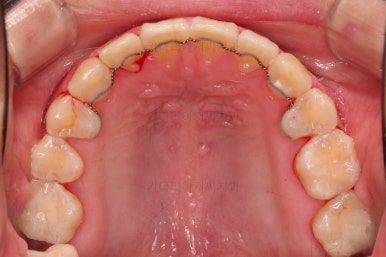

1. 초진

초진 시 입안의 모습입니다.

당장 눈에 띄는 부분은 아래 앞니 사이에 틈새가 있어 치석도 많이 쌓여있는 상황이고요.

윗니-아랫니를 각각 보면 치아가 썩고 부러져 뿌리만 남은 치아가 많이 보입니다.

남은 치아들도 곳곳에 충치가 보이고요.

또 전반적으로 앞니가 앞으로 밀려나와 뻐드러져 있는 모습도 관찰되네요.